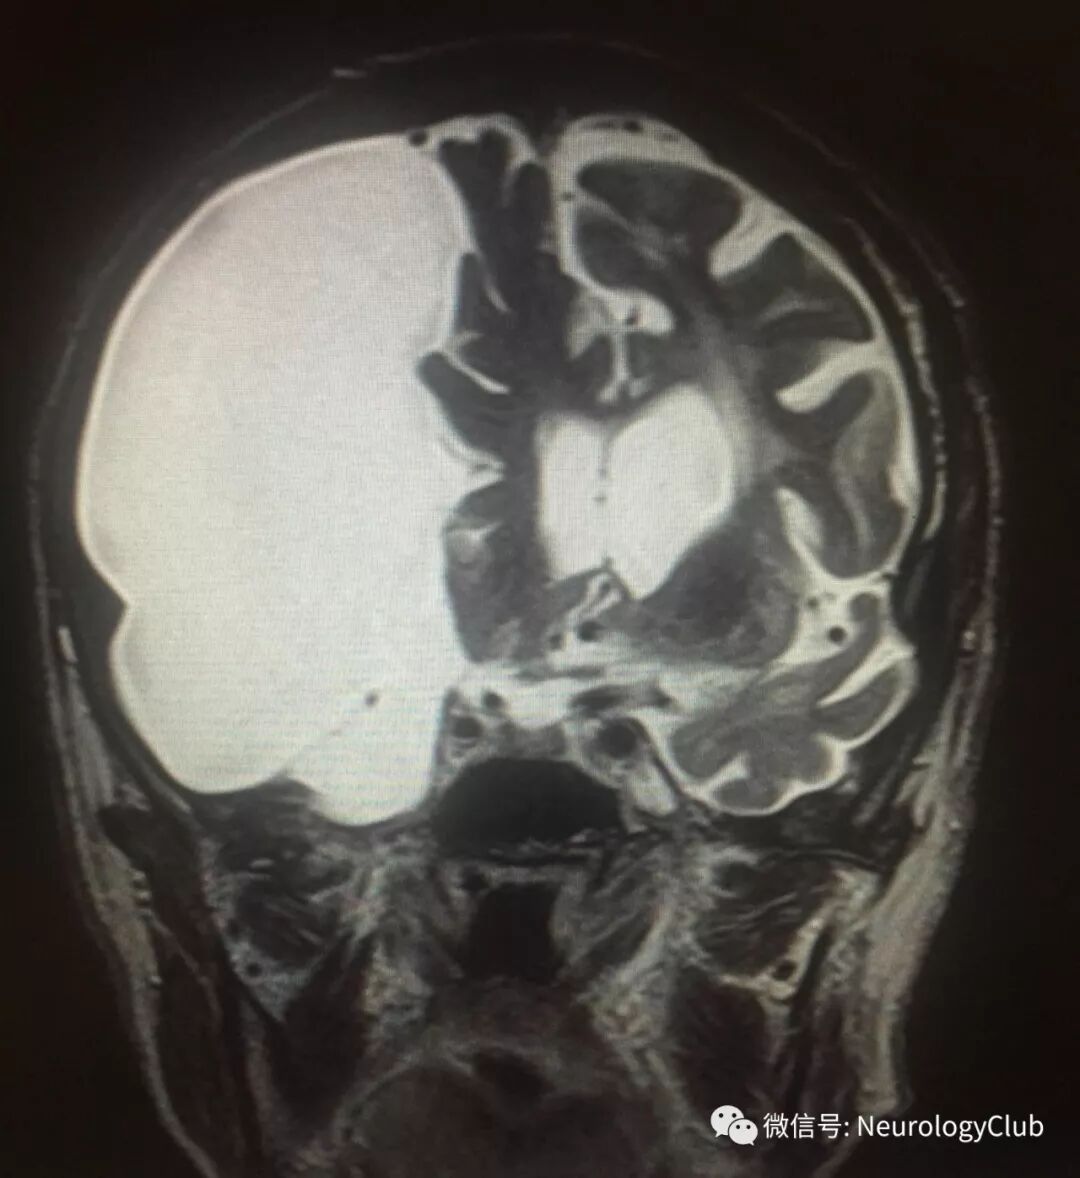

头颅MRI如下:

(图1:冠状位T2WI可见右侧大脑半球囊性病灶;有占位效应,伴中线移位和大脑镰下疝;在侧裂池分叉处可见大脑中动脉